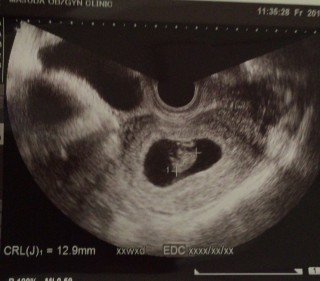

写真:7w6d:MKさん

12月の中旬に妊娠がわかり、12/25に心拍、胎嚢の確認ができ、6週目と判断されました。 それから2週間弱の今日下腹部のチクチクが気になり受診しました。 すると胎芽もはっきりと確認できました! 感動です?ちなみに今は7w6d明日で3か月目へ突入です。 8週目目前にしては12mmと、小さめと言われましたが、切迫流産の危険性も今のところは全くないみたいで、とりあえず一安心です、母子手帳も発行しに来週役所に向かうので、楽しみです!

高温期からの計算だと7w6dですが、CRL12.6なので大きさ的には7w3dだそうです。2週間前には確認出来なかった赤ちゃんも心拍も確認出来て感動しました!